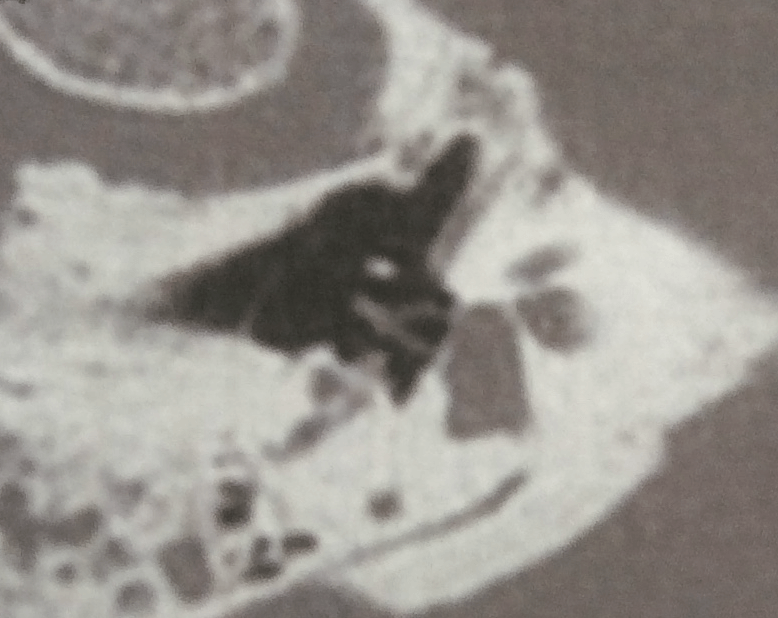

Hors-sujet quelques images de scanner pour comprendre l'articulation des 3 osselets avec l'ancienne et "nouvelle" dénomination selon la Terminologie anatomique de 1998, révisée en 2005 (dont il n'y a toujours pas de traduction française..): le malleus (que j'ai francisé en malléus, marteau), l'incus (et non uncus!, enclume) et enfin le stapes (pareil j'ai francisé en stapès, parfois écrit stapés, étrier).